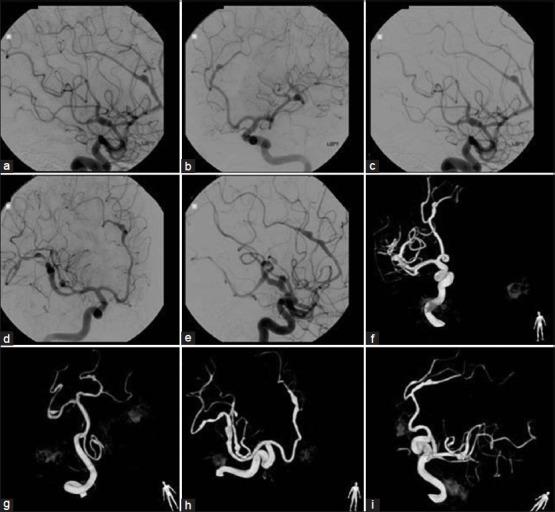

CASE DESCRIPTION

We describe the unique case of a 47-year-old female who developed multiple FIAs over a 6-year period without an obvious underlying pathology. The patient's medical history was significant for obesity, migraine headaches, insomnia, breast cancer, and chronic skin rash. Various diagnoses were explored including infectious etiologies, autoimmune vasculopathies, malignancy-related causes, connective tissue disorders, and underlying genetic conditions. However, all investigations, including aneurysm wall and skin biopsies were negative or deemed noncontributory toward making a definitive diagnosis.

病例描述

我们描述了一名47岁女性的独特病例,该患者在6年时间里出现了多个FIAs,且无明显潜在病理情况。患者的病史包括肥胖、偏头痛、失眠、乳腺癌和慢性皮疹。对各种诊断进行了探索,包括感染性病因、自身免疫性血管病变、恶性肿瘤相关病因、结缔组织疾病和潜在遗传疾病。然而,所有检查,包括动脉瘤壁和皮肤活检均为阴性或被认为对明确诊断无帮助。

结论

我们报告了一例不寻常的病例,一名患者脑血管造影正常,在6年时间里出现多个FIAs,且无明显潜在病因。鉴于目前该病的自然史尚不清楚,建议对该病例进行密切的临床和影像学随访。本文对关于多发性梭形颅内动脉瘤潜在病因的文献进行了综述。